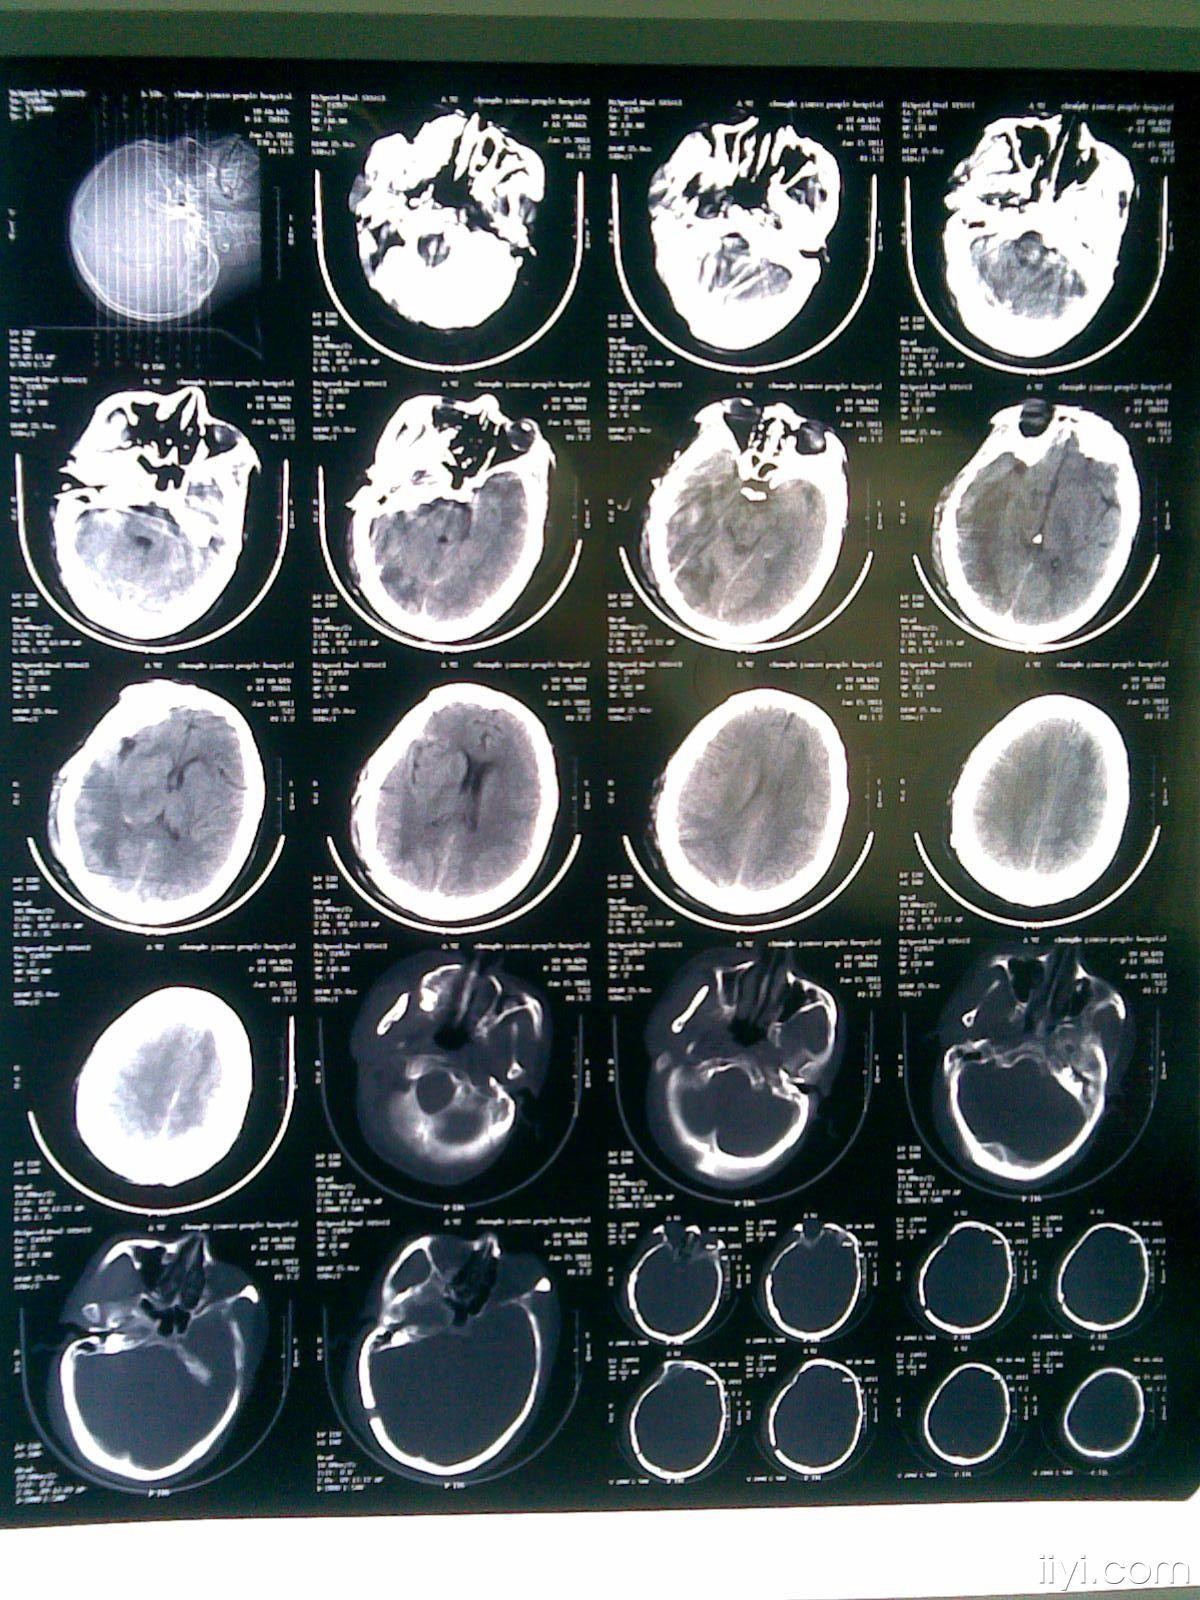

术前颅脑ct可见脑干出血.

第二次出血,2017年12月,ct片如下

术后第二天复查ct,再次吸出10ml,陈旧性血块

术前ct

手术后ct 显示脑干已被血块(黄)压扁 红箭头是术后之空气

患者拔管前复查头颅ct,显示颅内出血引流较彻底.

3d指导下小脑出血治疗一例